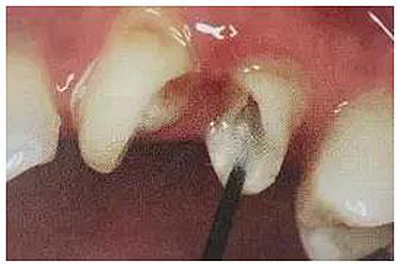

第一步,去除27的銀汞充填材料,發(fā)現(xiàn)髓腔破壞大,繼發(fā)齲明顯,牙體變色。

第二步,拆除26舊修復(fù)體,因為密合度高,拆冠費了不少時間。

拆冠對26的頰舌側(cè)肩臺有所破壞,牙齦少許損傷。暫時臨時牙修復(fù)保護基牙。